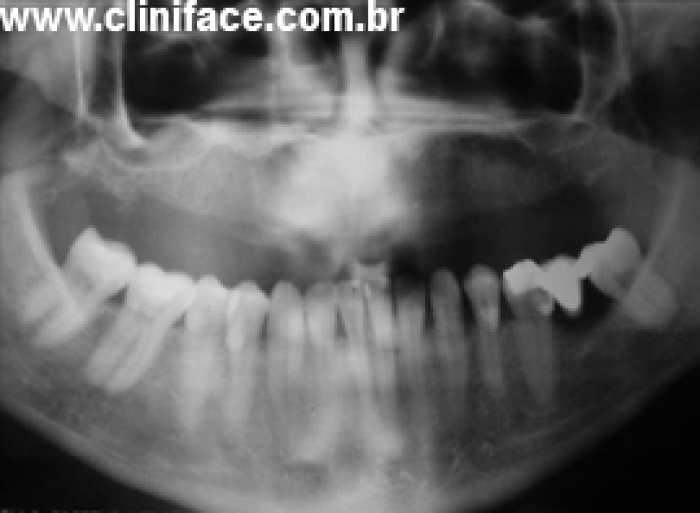

Raio X inicial